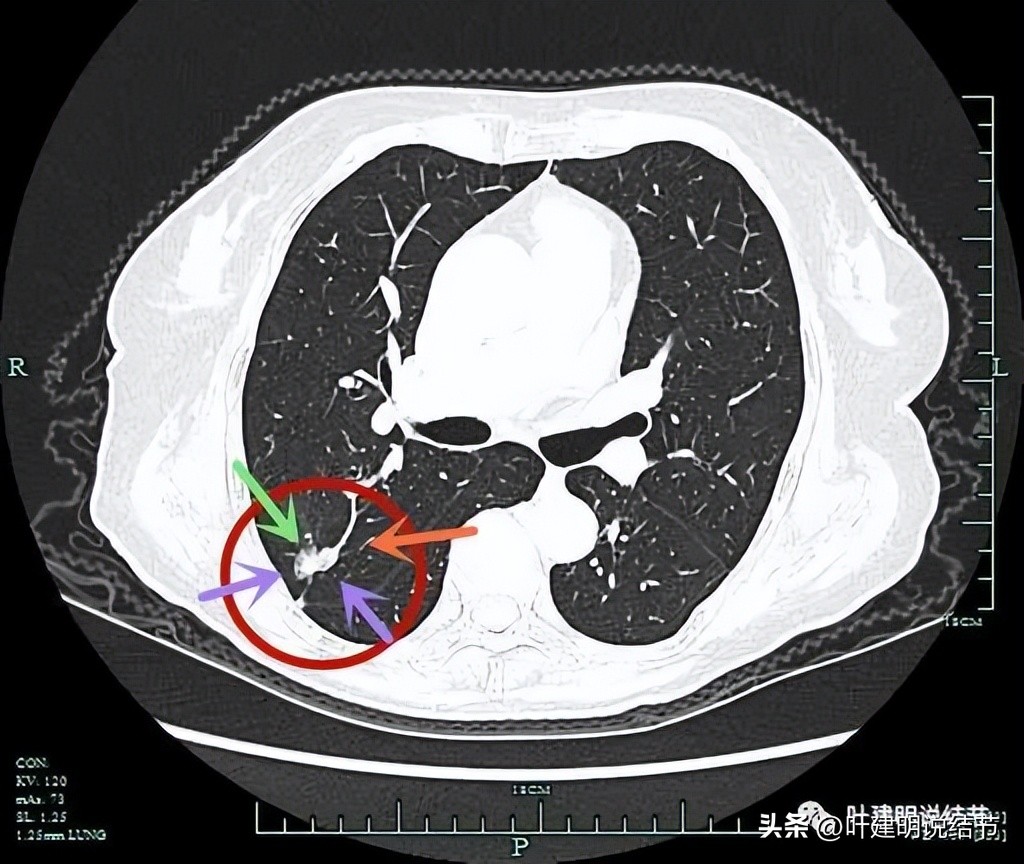

病灶有分叶(砖色箭头);边缘区有磨玻璃成分(绿色箭头);血管进入并异常增粗(桔色箭头)。

病灶磨玻璃成分(绿色箭头);紫色箭头所指处边缘较平,没有明显毛刺征;血管进入是异常增粗的(桔色箭头)。

边缘区略显模糊。

纵隔窗见病灶为实性密度。